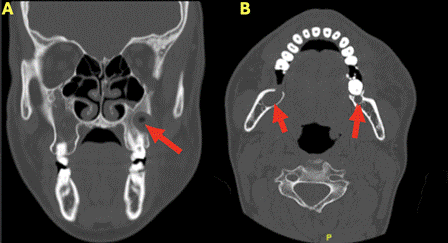

Vuelve a consultar en agosto del 2024 debido a un episodio de aumento de volumen hemifacial izquierdo, el cual fue tratado en el departamento de urgencias de otro recinto hospitalario, donde se realizó el tratamiento antibiótico y el drenaje del contenido purulento. Mediante la tomografía computarizada (TC) maxilofacial, se detectaron tres lesiones hipodensas con apariencia quística: una en la zona hemimaxilar posterior izquierda que correspondería a la recidiva de uno de los QO previamente tratados en el año 2021, y dos a nivel de ambos ángulos mandibulares (Figura 2). Se realizó la biopsia de estas lesiones confirmando el diagnóstico de QO, por lo que se decidió realizar la enucleación con osteotomía periférica de las lesiones mandibulares más pequeñas, en conjunto a la aplicación de SCM, y la canulización de la lesión maxilar para su descompresión y posterior enucleación.

Figura 2. Tomografía computarizada tomada en el Servicio de Urgencias, evidenciando tres lesiones hipodensas señaladas con una flecha roja. (A) Lesión hipodensa de apariencia quística ubicada en zona maxilar izquierda que se encontraba sobreinfectada, correspondería a la recidiva de lesión tratada en 2021. (B) Lesiones hipodensas de apariencia quística ubicadas en ambos ángulos mandibulares, lesiones que no se encontraban el 2021.